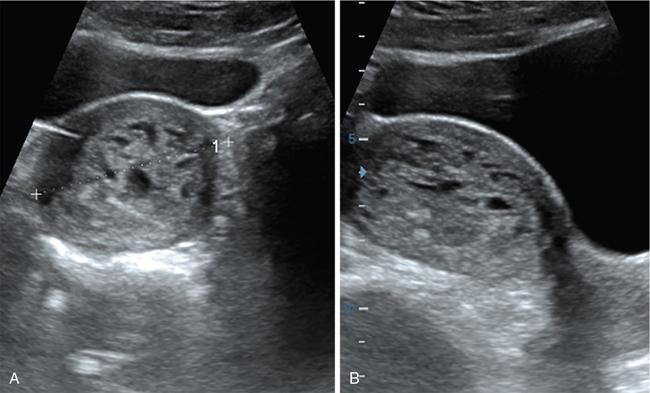

Venkatraman Indiran Bridging vessel sign Multiple vascular channels (white arrows) connecting uterus (black arrow) to an adjacent pelvic mass on imaging studies, is known as the ‘bridging vessel’ or ‘bridging vascular’ sign. Originally described on colour Doppler imaging, but also seen on computed tomography (CT) or magnetic resonance imaging (MRI). Helps in differentiating a mass of uterine origin, typically a subserosal fibroid, from other pelvic masses. Sensitivity and specificity of ‘bridging vessel sign’ in identifying subserosal fibroids range from 90% to 100%. (Best seen when subserosal fibroid is larger than 3 cm in diameter.) Ovarian masses invading the uterus may rarely produce a falsely positive bridging vessel sign. Broccoli sign Submucosal uterine leiomyoma prolapsing into the endocervical canal, along with its stalk in the uterine cavity on sagittal T2-weighted images together is called as ‘broccoli sign’ (white arrow). Submucosal uterine leiomyoma Bunch of grapes Intrauterine mass with cystic spaces without any associated foetal parts on ultrasound (white arrows) classically gives a ‘snow storm’ or ‘bunch of grapes’ appearance. Complete hydatidiform mole Hourglass sign Deep infiltrating endometriosis (DIE) affecting the posterior urinary bladder wall, usually in the midline, causes loss of its distensibility, resulting an hourglass configuration of urinary bladder. Deep infiltrating endometriosis (DIE) Hyperechoic line sign Normal endometrium surrounding the endometrial polyp on ultrasound appear as a hyperechoic rim on transvaginal ultrasound is called as ‘hyperechoic line sign’. Hyperechoic line sign represents a focal intracavitary lesion. Endometrial polyp Indian head dress sign/moose antler sign In deep infiltrating endometriosis (DIE), adhesions between the anterior wall of rectosigmoid and posterior wall of uterus, stretches the muscular layer of the bowel and creates an infiltrative nodule with parallel lines that extend from the adhesion to the rectosigmoid. This is called as ‘Indian head dress sign/moose antler sign’ (white arrow). This is seen on sagittal T2-weighted images as well as transvaginal ultrasound. Deep infiltrating endometriosis (DIE) Interstitial line sign An echogenic line that extends into the upper regions of the uterine horn and borders the margin of the intramural gestational sac is called as the ‘interstitial line sign’ (white arrow). Seen best on transabdominal/transvaginal ultrasound. Specific finding of interstitial pregnancy Mushroom cap sign Mushroom-shaped lesion which is seen displaced into the bowel lumen in patients with solid invasive endometriosis of the rectosigmoid colon on axial or sagittal T2-weighted MRI is called as ‘mushroom cap sign’ (red box and white arrow). Low signal intensity base of the mushroom corresponds to hypertrophy and fibrosis of the muscularis propria, whereas the high intensity cap represents oedematous mucosa and submucosa. Deep infiltrating endometriosis (DIE) Pedicle artery sign Feeding vessel sign Central vessel entering the endometrium from the surrounding myometrium colour Doppler imaging of the endometrium in endometrial polyps is called as pedicle artery sign (white arrow). Endometrial polyps in women with postmenopausal bleeding. (Sensitivity of 76.5%; specificity of 95.3%.) Popcorn ball calcification Dense, amorphous calcifications of uterine fibroids seen on the plain radiographs is called as ‘popcorn calcification’ (white arrow). Confluent, coarse calcification constitutes the most specific radiographic sign of a benign uterine fibroid; but only 10% or fewer of fibroids show calcification. Question mark sign of uterus The uterine corpus that is flexed backward with the fundus of the uterus facing the posterior pelvic compartment and the cervix directed anteriorly toward the urinary bladder, is called as question mark sign of uterus (white arrow). Also called as comma-shaped uterus. 93% specificity and 75% sensitivity in diagnosing adenomyosis uterus. Sliding organs’ sign When the uterus and ovaries glide freely over the posterior and anterior organs (such as rectum and urinary bladder, respectively) during real-time dynamic transvaginal sonography, it is called as ‘positive sliding organs’ sign’. In case of adhesions due to endometriosis, free gliding of organs is absent and is called as negative sliding sign. Snowstorm sign Grainy appearance with low-level homogeneous internal echoes which move slowly downward due to their viscosity seen in endometrioma on transvaginal ultrasound is called as snowstorm sign. Endometriomas Split fibre sign Presence of curvilinear T2 hypointense strands within the degenerated leiomyoma separated by the fluid accumulation and oedema is called as the ‘split fibre’ sign. Split fibre sign on T2-weighted MRI can be used to differentiate hydropic degeneration from other conditions like malignant change. Three-line sign or triple line sign or trilaminar appearance Shortly before ovulation, two additional bright linear echoes outline two hypoechoic layers of endometrium with a central hyperechoic line in the endometrium (white arrow). It is called as the ‘three-line sign’ or ‘triple line sign’ or trilaminar appearance. A triple-line pattern with a moderate endometrial thickness is associated with a good clinical outcome on in-vitro fertilization. Venetian blind shadowing Also known as ‘rain shower’ appearance Heterogeneous myometrial appearance due to hyperechoic heterotopic endometrial tissue and hypoechoic hyperplastic smooth muscle appearing as vertical linear bands of shadows on ultrasound is called as ‘Venetian blind shadowing’. Classically described in uterine adenomyosis; sometimes in uterine fibroids also. Bead on strings sign Thickened endosalpingeal longitudinal folds within a dilated fallopian tube without wall thickening appears as small mural nodules on cross-sectional images on ultrasound is called as ‘bead on strings’ appearance. Seen in chronic salpingitis Beaded tube Multiple constrictions along the course of fallopian tube may form due to scarring is seen in genitourinary tuberculosis and shows a ‘beaded’ appearance. Female genital tuberculosis Cogwheel sign Thickened endosalpingeal longitudinal folds within a dilated fallopian tube with thickened wall appears as small mural nodules on cross-sectional images across the long axis of the fallopian tube on ultrasound (white arrows) produce a characteristic ‘cogwheel’ appearance. Seen in acute salpingitis. The presence of thickened longitudinal folds is pathognomonic for hydrosalpinx. Cobblestone tube Rounded filling defects in cases of fallopian tube tuberculosis are called as the cobblestone pattern. Is an effective radiographic sign of intraluminal scarring and adhesions. Female genital tuberculosis Golf club tube Occlusion of the isthmus or fimbrial end of the fallopian tube and filling up of the tube with serous or clear fluid produces a moderate dilatation at the fimbrial end, produces a ‘golf club–like appearance’. Female genital tuberculosis Halo sign Thin radiolucency seen separating the loculated peritubal collection from the dilated tube, is known as the ‘halo sign’. This radiolucent halo represents the thickened wall of the tube. Female genital tuberculosis Incomplete septation sign Thin linear structures appearing to protrude into the tubular cystic adnexal structures, but not touching the opposite walls is called ‘incomplete septation sign’ of hydrosalpinx. Apparent septae are due to apposition of the inner walls of the dilated and folded fallopian tube. Hydrosalpinx Pipe stem tube Rigid contour of the fallopian tube seen in cases of fallopian tube tuberculosis is called as ‘pipe stem appearance’. Female genital tuberculosis Leash sign Typical eccentric leash of vessels on colour Doppler (white arrow) showing a low resistance placental type of flow on spectral Doppler in fallopian tube ectopic pregnancies is called as leash sign.